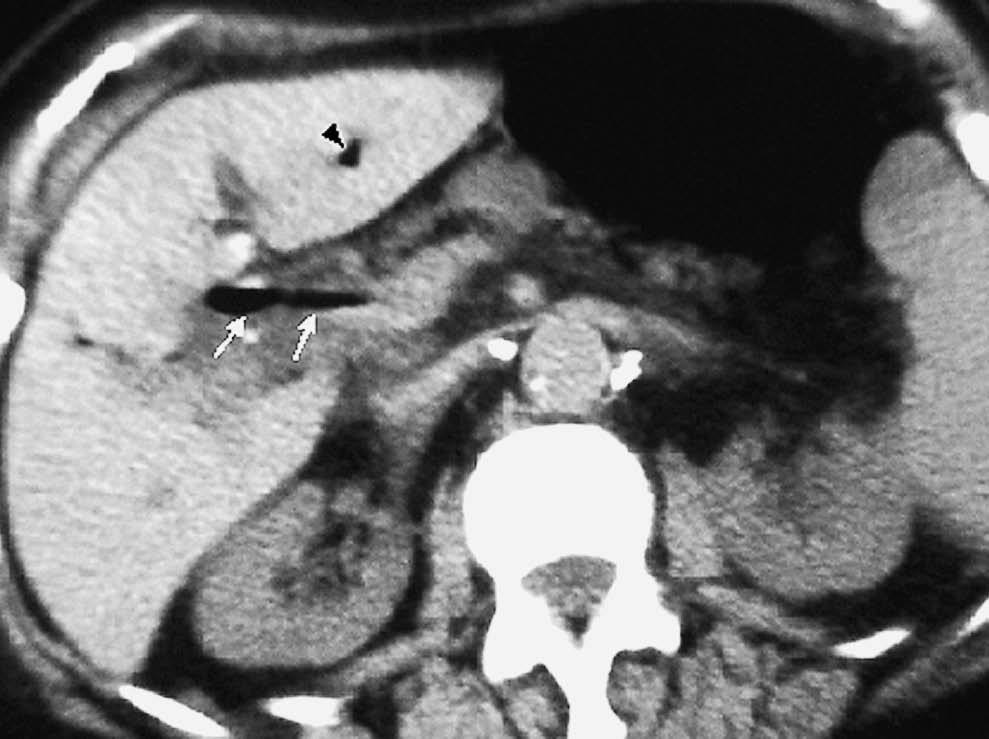

La colecistitis también puede afectar al duodeno, produciendo un engrosamiento de pared secundario a la extensión de la inflamación vesicular. Dicha inflamación puede provocar un absceso de pared duodenal (fig. 13). La existencia de un nivel hidroaéreo en la TC sugiere que se ha producido una comunicación con la luz intestinal. La inflamación puede progresar y perforar la pared duodenal ocasionando una fístula bilioduodenal, identificándose en la ecografía como un trayecto hipoecoico con paso de contenido ecogénico (gas) entre vesícula y duodeno. También se puede observar la presencia de aire en vesícula, que puede extenderse al resto de la vía biliar (neumobilia) (fig. 14). La salida de la colelitiasis a través de la fístula y su impactación en el tracto intestinal puede producir un íleo biliar20.

Fig. 14--Fístula bilioduodenal. (A) Ecografía. (B) Tomografía computarizada sin contraste intravenoso. En ambas técnicas se identifica el trayecto fistuloso (flechas) entre vesícula y duodeno. Asocia neumobilia (punta de flecha).